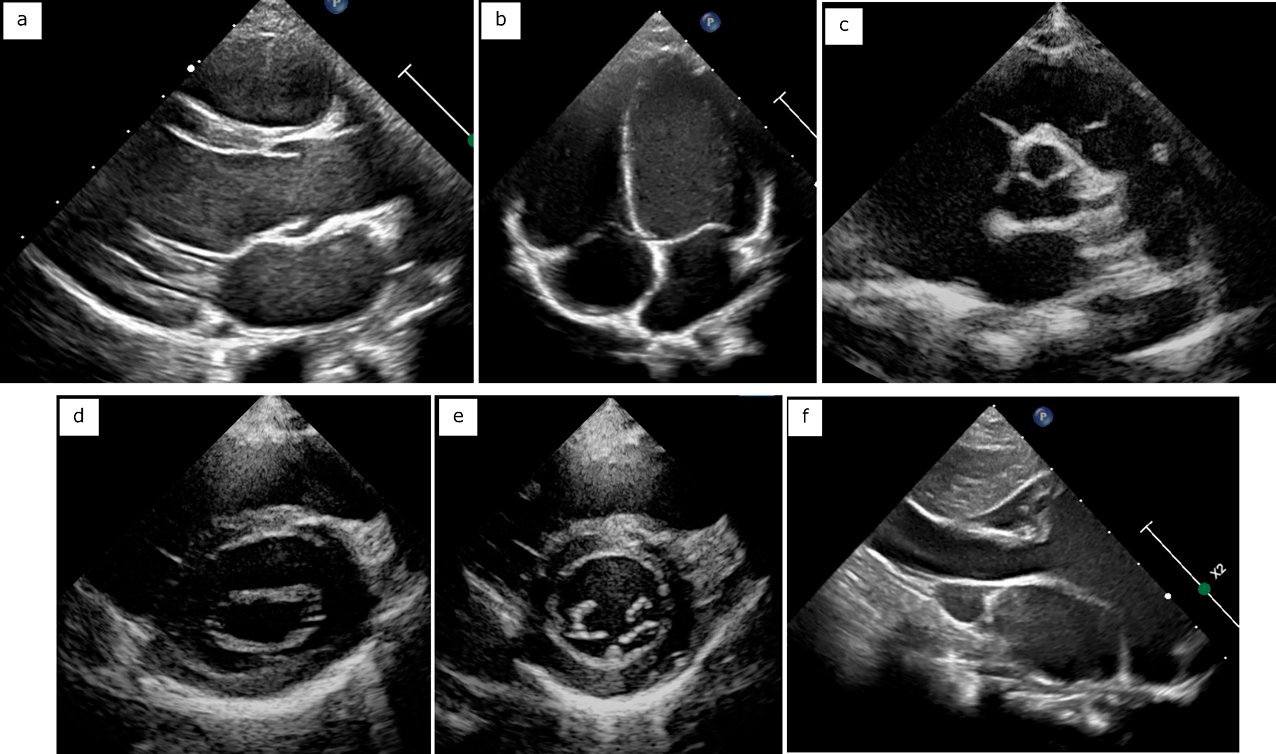

メジカルビュー社|循環器内科|循環器診療 ザ・ベーシック 心。病態・類似疾患別心エコー図検査のルーティン[Web動画付。心臓超音波検査(心エコー / Echocardiography / UCG) - 神戸き。「臨床心エコー図学」吉川 純一定価: ¥ 35000ご覧いただきありがとうございます。たらこ様 臨床工学技士国家試験問題解説集 8回分。歯科CBT対策 CBT PASS 問題集1 基礎系・連問 第7版。書き込みなどはありません。